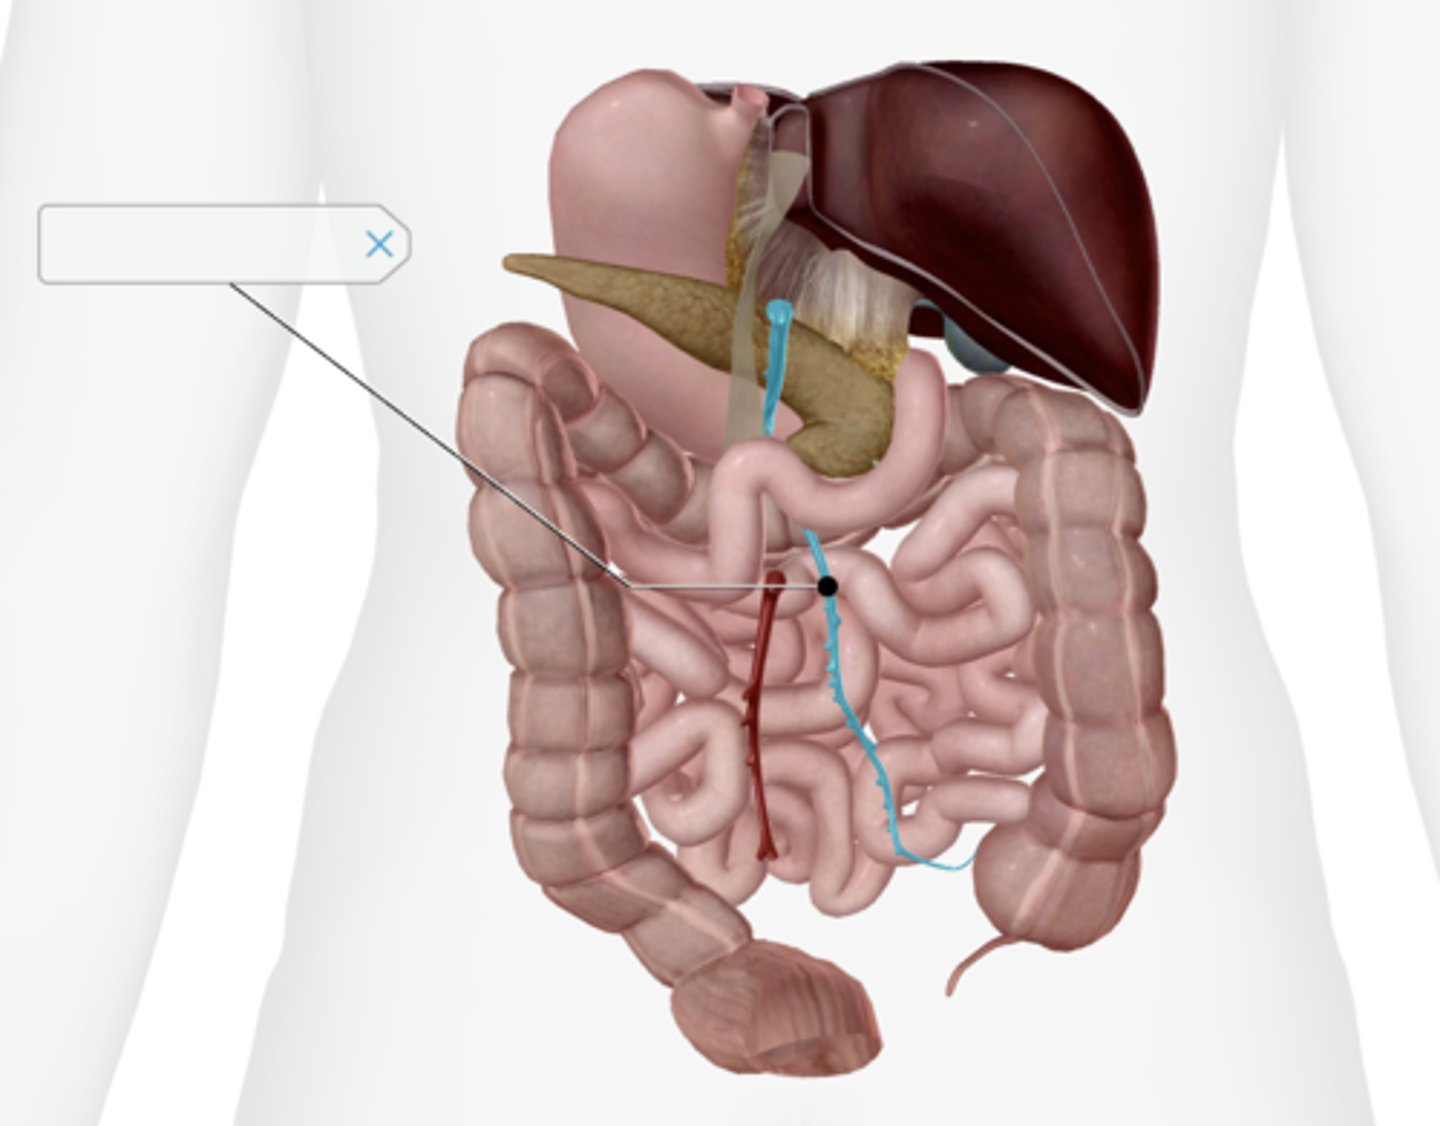

Jejunum

Ileum

Superior mesenteric artery